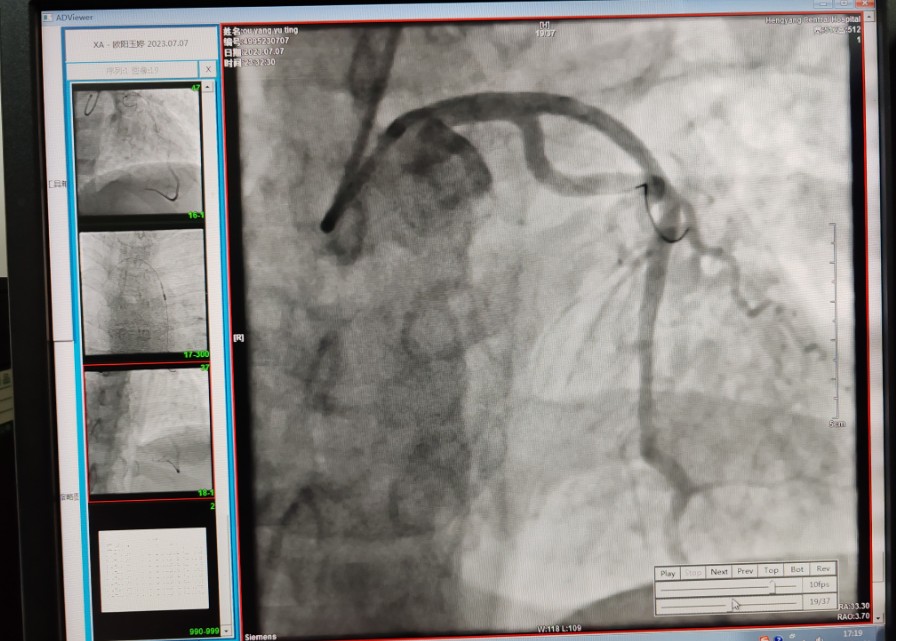

22:29分患者經(jīng)院內(nèi)綠色通道送達(dá)導(dǎo)管室,手術(shù)由雷剛副主任醫(yī)師主刀,楊繼賀副主任醫(yī)師為第一助手,介入技師及護(hù)士密切配合,聞?dòng)嵍鴣淼内w慶禧主任醫(yī)師坐鎮(zhèn)協(xié)調(diào)指揮。22:37分手術(shù)開始,冠脈造影顯示心臟上最重要的一條冠狀動(dòng)脈-前降支開口齊頭閉塞,血管粗大且血栓高負(fù)荷,非??简?yàn)介入術(shù)者的手術(shù)能力,一旦發(fā)生冠脈無(wú)復(fù)流或操作不慎血栓帶入回旋支導(dǎo)致循環(huán)崩潰,病人幾乎無(wú)生還希望;此時(shí),患者手術(shù)臺(tái)上仍持續(xù)胸痛,且血氧飽和度在高流量吸氧狀態(tài)下不到80%,雷剛副主任醫(yī)師一方面指揮鎮(zhèn)靜鎮(zhèn)痛及抗心衰治療,一方面緊急啟用IABP(主動(dòng)脈球囊反搏),然后精細(xì)操控細(xì)如發(fā)絲的介入導(dǎo)絲迅速通過病變,并予冠脈球囊擴(kuò)張、冠脈內(nèi)溶栓、抗痙攣藥物使用、植入冠脈支架,最終成功開通“罪犯”血管,且無(wú)手術(shù)并發(fā)癥發(fā)生,整個(gè)過程張弛有度、快慢結(jié)合、一氣呵成。患者術(shù)后胸痛明顯好轉(zhuǎn),血氧飽和度上升至96%,術(shù)后1天轉(zhuǎn)出監(jiān)護(hù)病房,第3天拔出IABP,目前已康復(fù)出院。